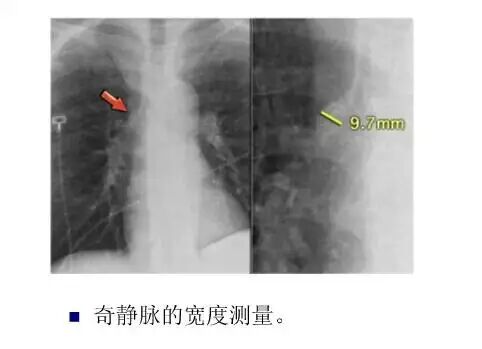

平片如何看心衰